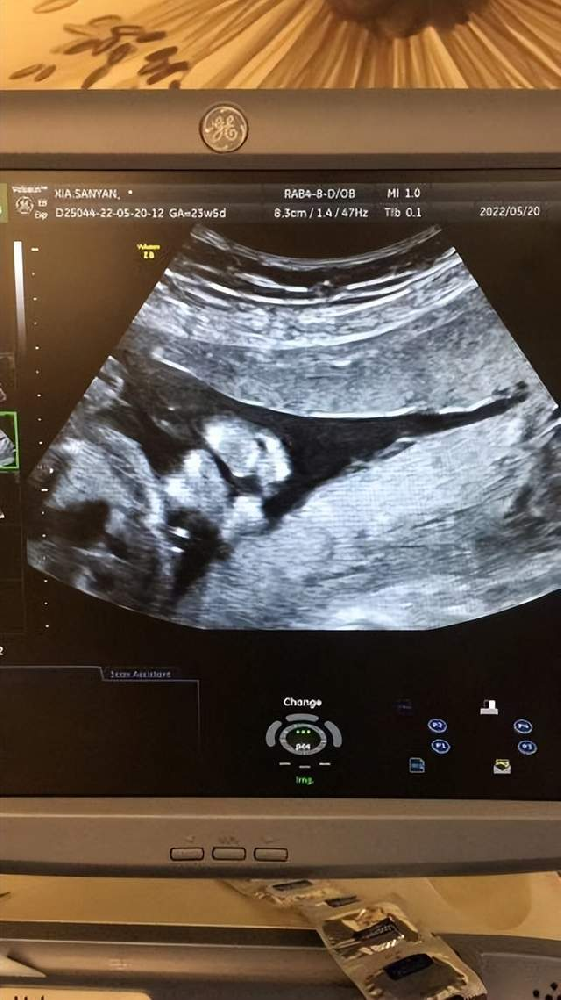

新生命的誕生對(duì)于一個(gè)家庭來(lái)說(shuō)是再幸福不過(guò)的一件事。隨著生育政策的放開(kāi),越來(lái)越多的家庭選擇生育二胎。但在迎接新生命的同時(shí),許多“二胎”孕婦認(rèn)為自己已經(jīng)是“熟手”,···